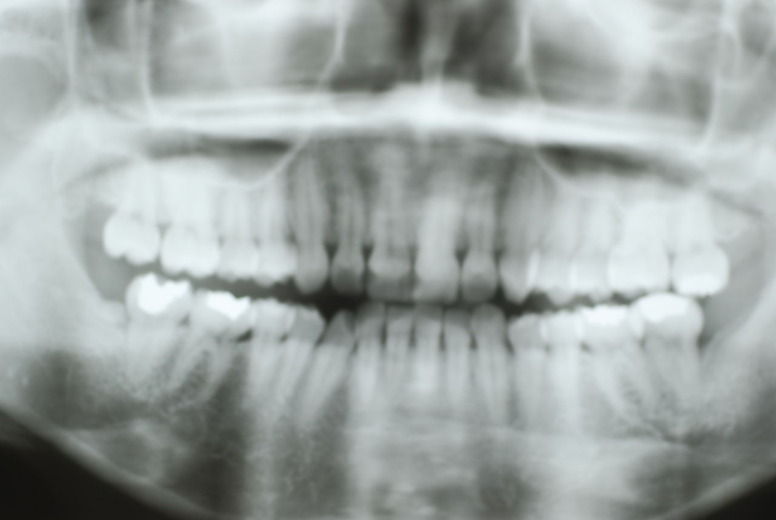

14年歯前、歯の神経が腐り、神経を除去したまま来なくなった現在大学生の女性

歯周病になっていましたが、少し色が黄色くなっているだけで比較的綺麗な歯の状態です。

平成9年来院神経を取り、同時に歯周病の話をしてそのまま来なくなっていたかたですが、たまたま一部欠けてきました。それで来院。

平成9年![40af2ca7-s[1]](https://livedoor.blogimg.jp/netdental/imgs/0/d/0d02b3dc.jpg)